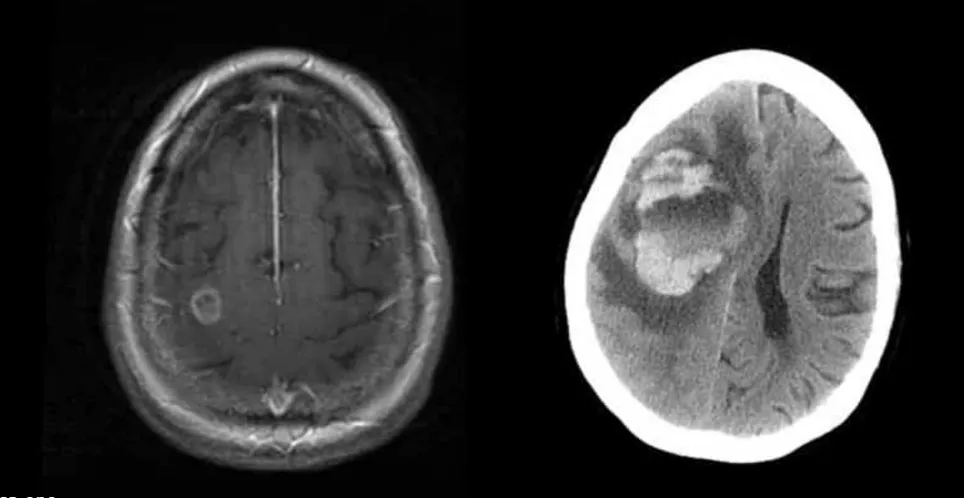

69-летняя женщина из Сиэтла была госпитализирована в отделение неотложной помощи больницы с приступом, похожим на инсульт, пишет The Seattle Times. Врачи провели компьютерную томографию ее мозга, пытаясь определить причину, предполагая наличие опухоли.

Но исследование ткани, взятой из ее мозга во время операции, показало, что причина не в опухоли.

«Когда я оперировал эту даму, часть ее мозга размером с мяч для гольфа оказалась кровавой кашей», — сказал д-р Чарльз Коббс, нейрохирург. «В ее мозге мы обнаружили микроорганизмы, которые пожирали клетки мозга. Когда мы сделали анализ, оказалось, что это были амебы».

Женщина заболела гранулематозным амебным энцефалитом после того, как прополоскала нос водопроводной водой. К сожалению, спасти ее не удалось.